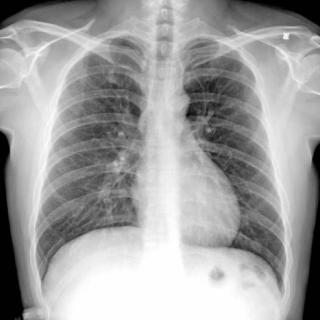

53:10 肺癌-体检、预防(别抽烟!)

60:15 绝大多数的肺癌,根本就没有症状